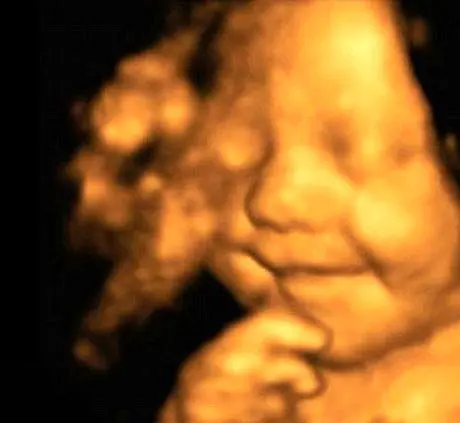

لبخندی به پهنای صورت، این اولین تصویر ثبت شده از نوزادی است که حتی پیش از ورودش به این دنیا به تمامی آن چیزی که…